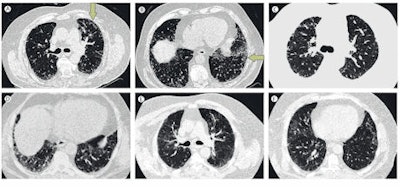

Click image to enlarge.

High-resolution axial CT images of upper and lower lung. A-B: Usual interstitial pneumonia; images show peripheral predominant, basal predominant reticular abnormality with mild subpleural honeycombing (B, arrows). The extent of honeycombing is < 5%. C-D: Possible usual interstitial pneumonia; images show peripheral predominant, basal predominant reticular abnormality without honeycombing. E-F: Inconsistent pattern of usual interstitial pneumonia; images show upper lung predominant abnormality characterized by ground glass abnormality with mild reticular abnormality. Images courtesy of Dr. Ganesh Raghu, reproduced with permission from the Lancet Respiratory Medicine.